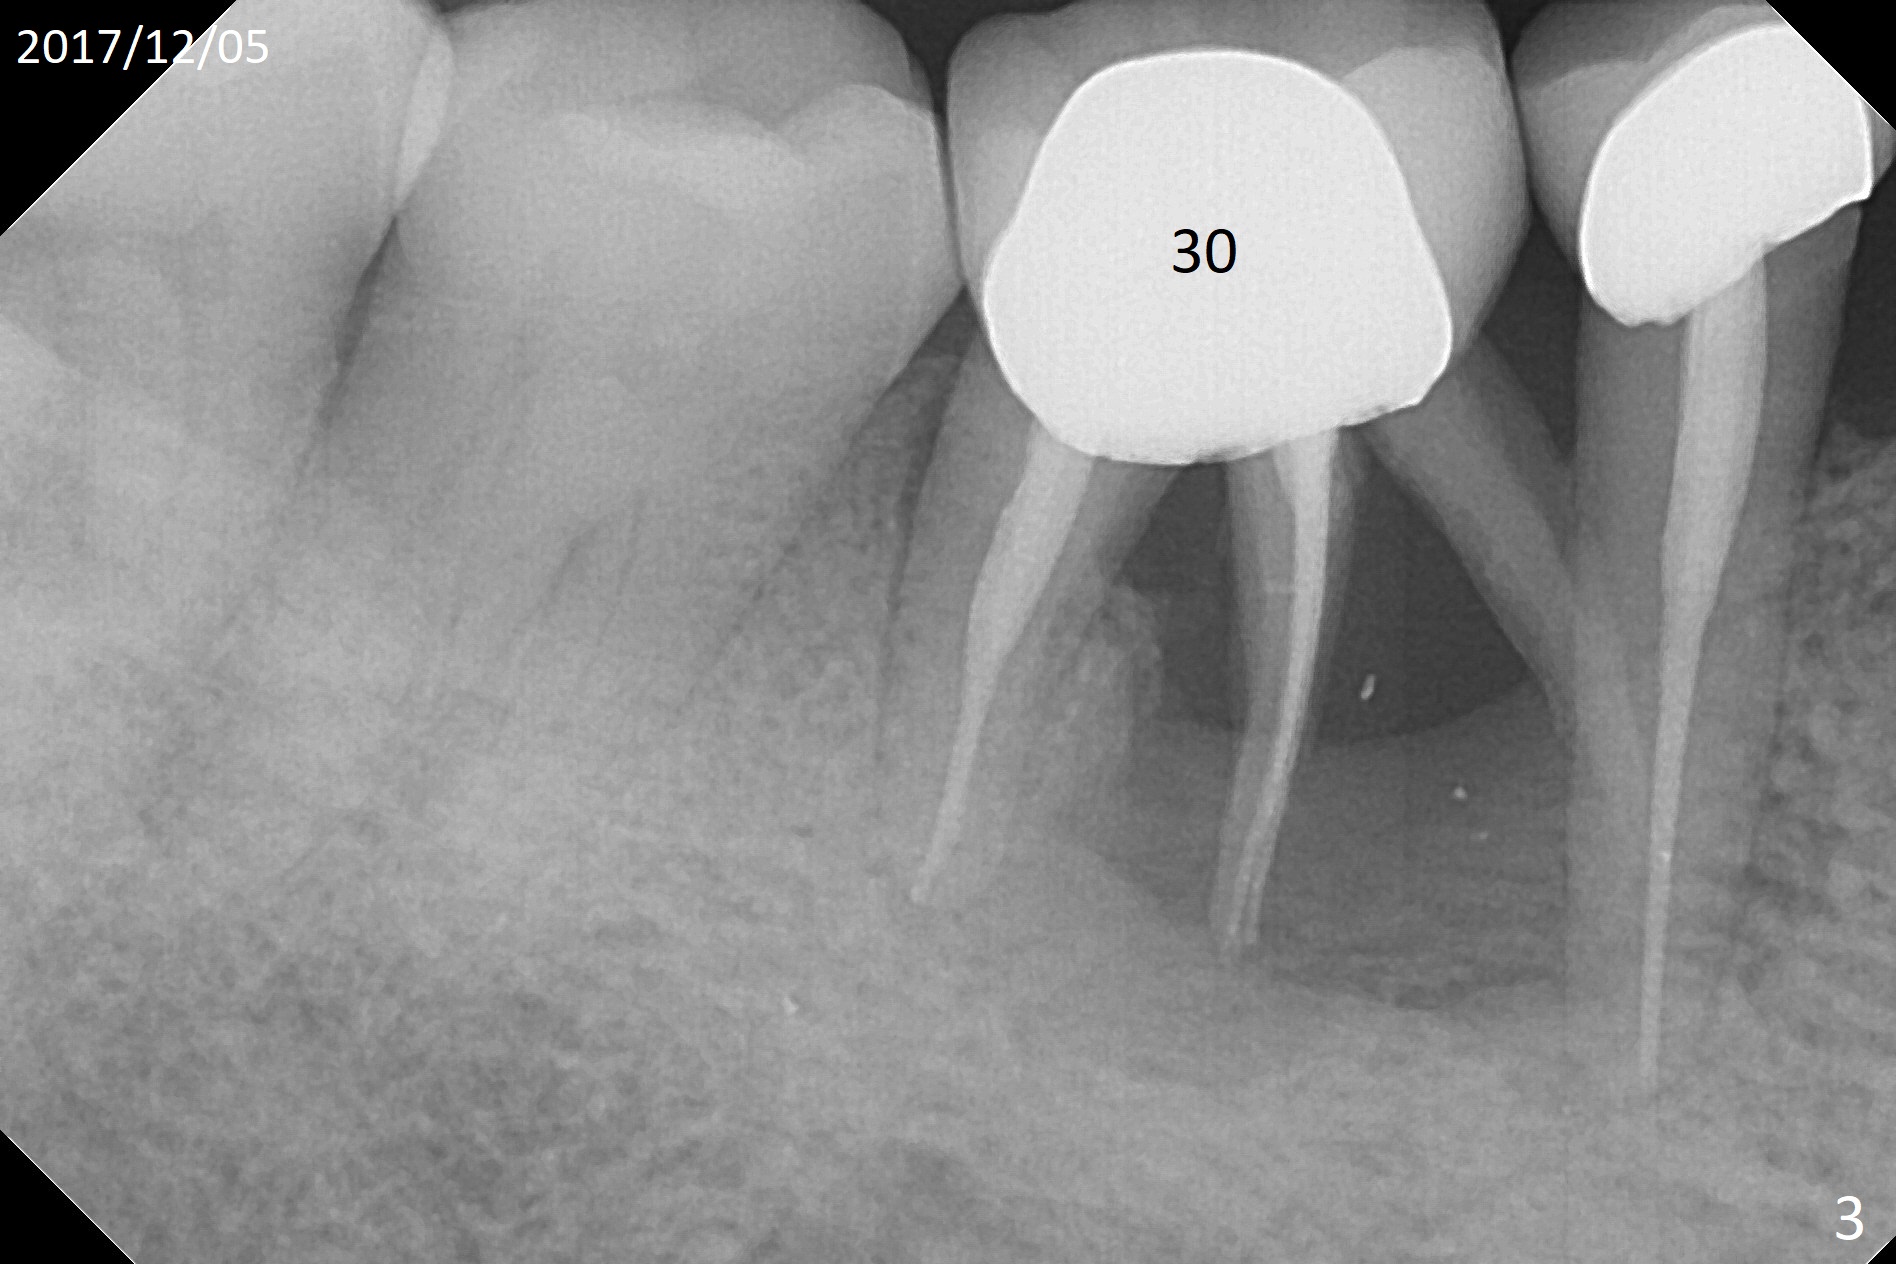

A 66-year-old woman is a bruxer/grinder. She loves chewing bone and eating nuts. The tooth #2 has exfoliated on its own, while the tooth #3 had periradicular bone loss (Fig.1). The upper left FPD is loose because of root fracture at #13 (Fig.2 >). Note the long alveolus. The mesial root of the tooth #30 has been fractured with severe bone resorption for the last 34 months (Fig.3). After extraction, initiate osteotomy in the middle of the socket irrelevant of the septum (Fig.4 red line). Take a PA or panoramic X-ray with a parallel pin immediately. When drills approaches the septum, use Magic Expanders to push the septum distal prior to resuming drills so that a 4.5x13 mm implant (Fig.5 green) is supported by the distally-displaced septum (arrow). The small implant is chosen so that there is room for bone graft, since the buccal and/or lingual plates are most likely defective mesially.